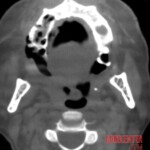

Further examinations, including blood tests, did not reveal diabetes or other common conditions that could explain the symptoms. However, it was evident that the body was fighting a severe infection. A crucial turning point came with a CT scan, which revealed extensive damage to the maxillary bone and spread of inflammation into the paranasal sinuses, including the deeper ones. Fortunately, the brain and eye sockets were not yet affected.